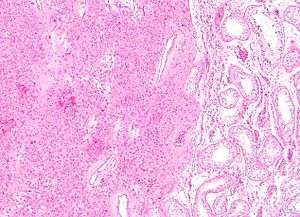

Low magnification micrograph of a Leydig cell tumour. H&E stain. | |

Intermediate magnification micrograph of a Leydig cell tumour. H&E stain.

High magnification micrograph of a Leydig cell tumour. H&E stain.